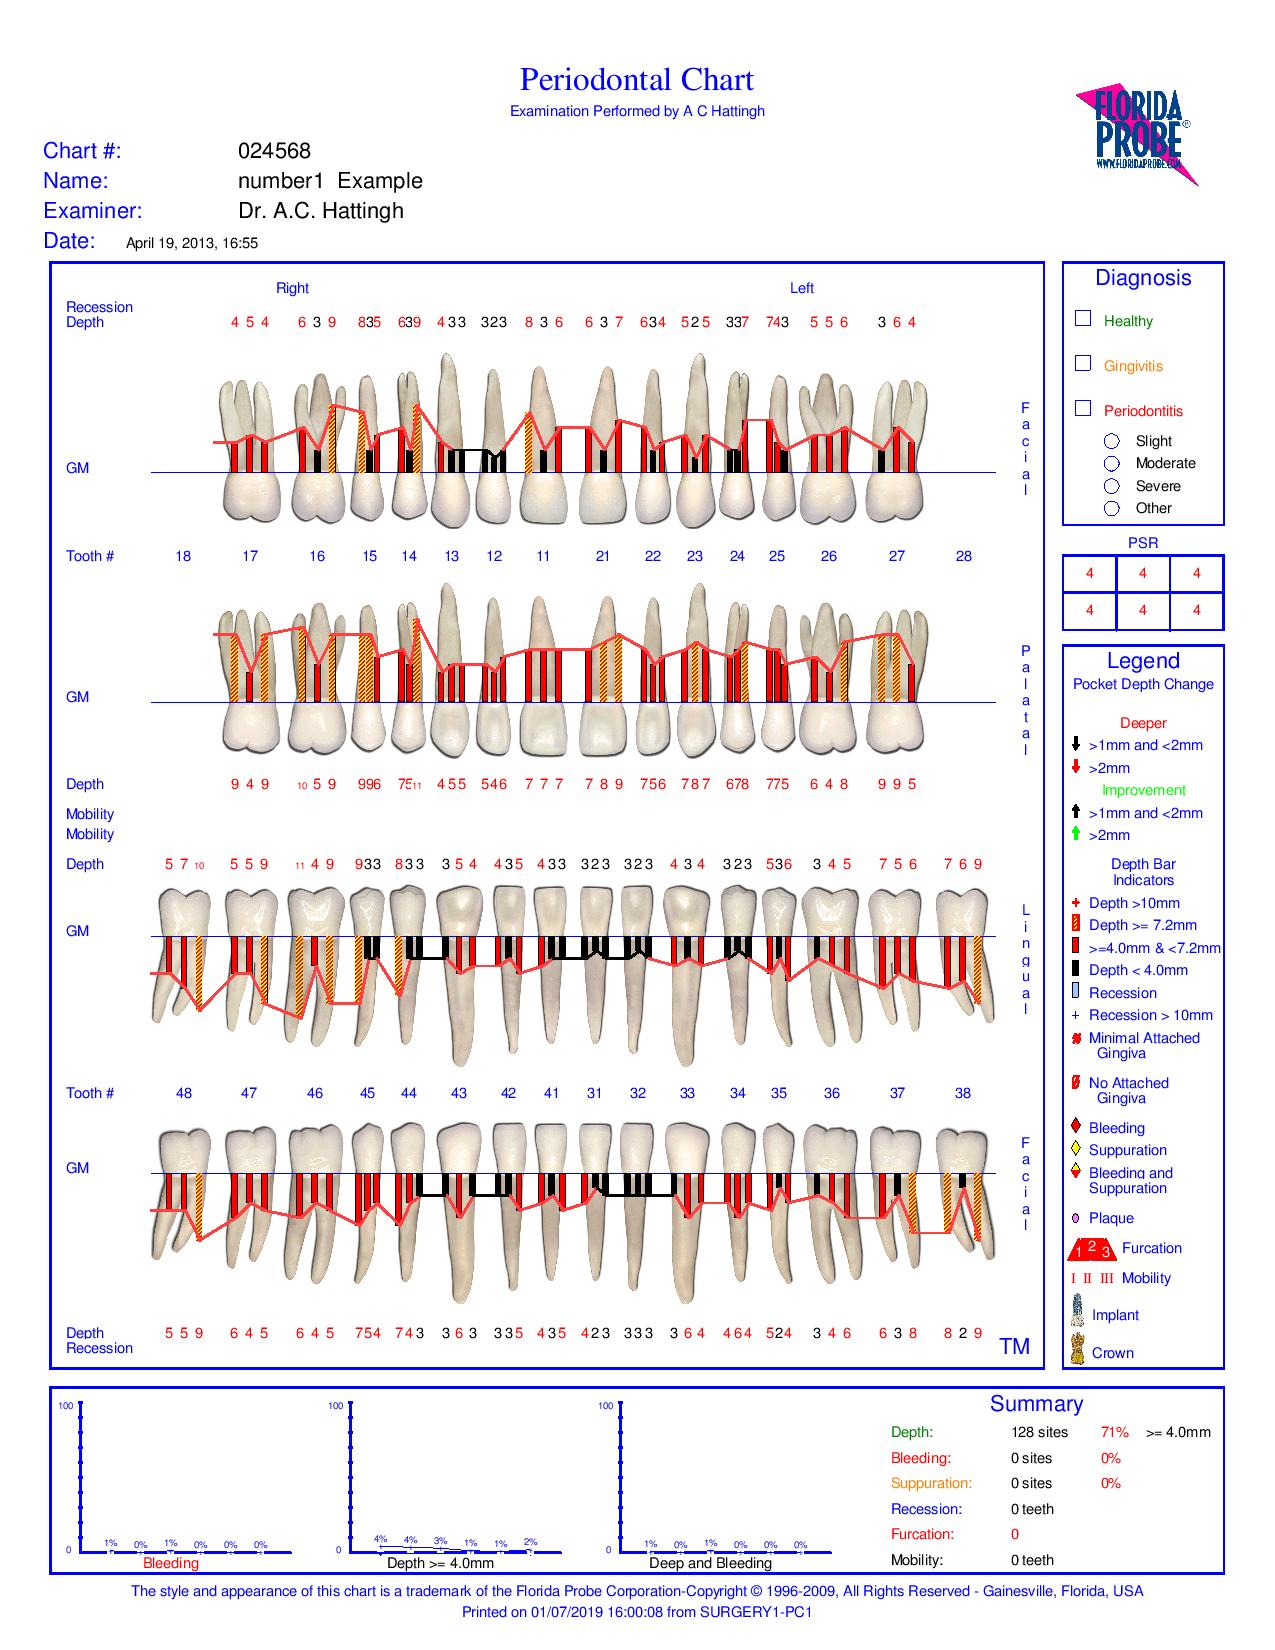

André Hattingh is a periodontist who dedicates his practice to the replacement of teeth with dental implants and to the treatment of gum disease (periodontitis).